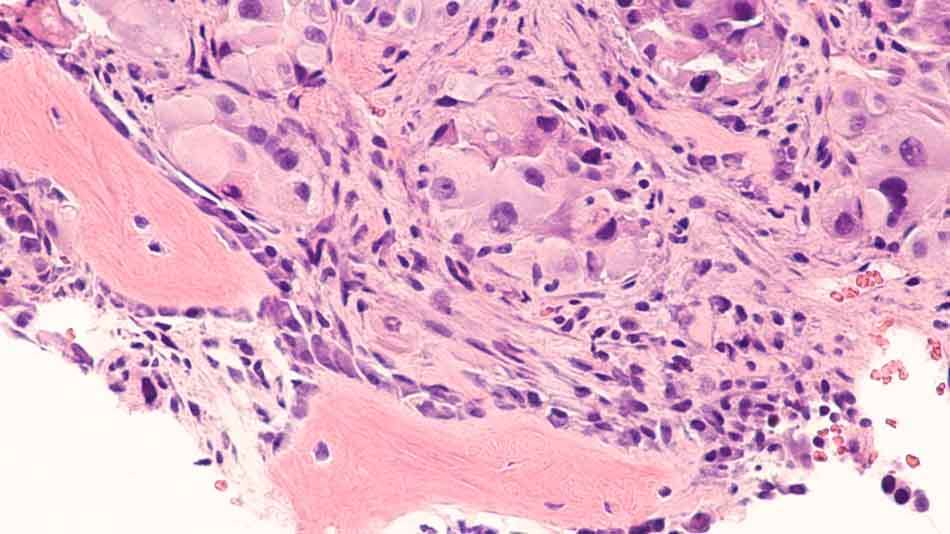

Sıklıkla 40 yaş sonrası ortaya çıkan kemik metastazı mevcut kanserin ilerlemiş olduğunu gösteriyor. Bu hastaların alanında uzman hekimler (Ortopedik Onkoloji hekimi, Tıbbi ve Radyasyon Onkolojisi, Patoloji, Radyoloji ve Nükleer tıp) tarafından değerlendirilip tanı ve tedavisine karar verilmesi gerekiyor. Doç. Dr. Gümüştaş, kemik metastazlarının tüm kemiklerde gelişebilmekle birlikte en sık omurga, pelvis (leğen kemiği), femur (uyluk) ve humerus (kol) bölgesinde görüldüğünü belirterek şöyle konuşuyor: “ Kemik metastazı tanısının konulmasının hayati önemi vardır. Özellikle kemiğin kendisinden kaynaklanan tümörlerden ve hastanın mevcut tümöründen başka bir odaktan kaynaklanmadığı ortaya konulmalıdır. Aksi taktirde hastanın yaşamını ciddi şekilde olumsuz etkileyecek geri dönüşümsüz hatalara yol açılır.”